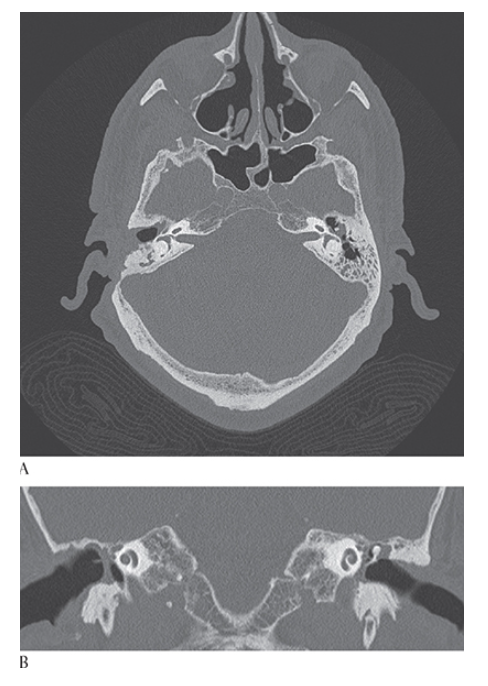

What is A

Cholesteatoma. Axial NECT of the temporal bones shows soft tissue in the left middle ear located lateral to the ossicles in the epitympanum (Prussak space). Mastoidectomy has previously been performed on the right. Coronal CT

What is B

Cholesteatoma. Axial NECT in same patient shows soft tissue in left middle ear within Prussak space of the epitympanum with blunting of the scutum. Right mastoidectomy is present.